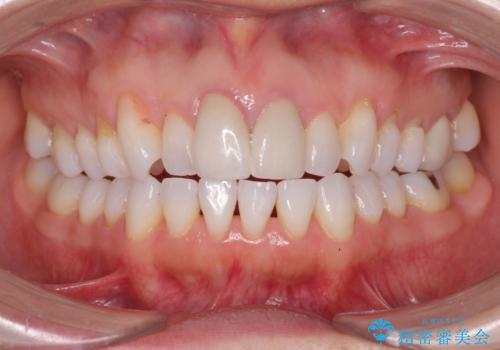

- メンテナンスでいらっしゃった患者様です。

歯を保護するためのナイトガードを装着していきます。

厚みのあるナイトガードを調整することで、夜間の歯ぎしりにより歯にかかる強い力を分散させることができます。